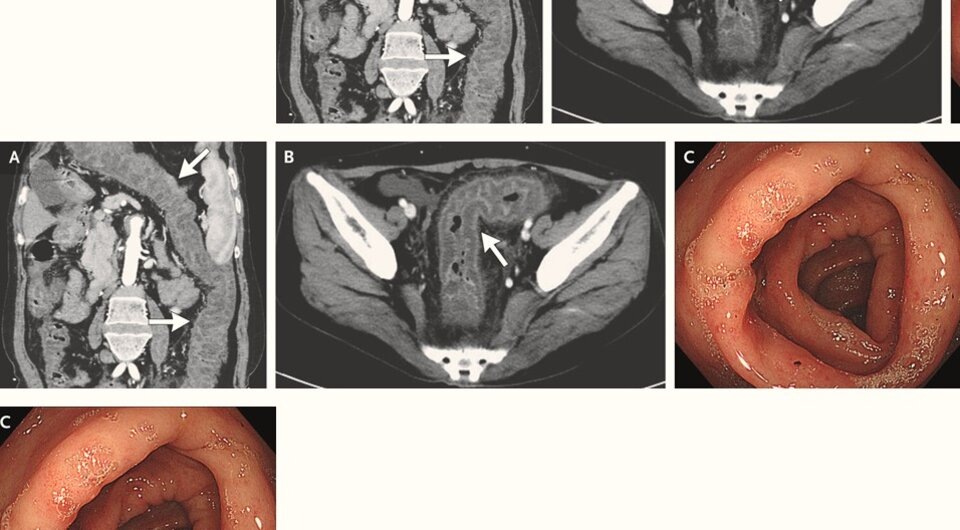

В китайскую больницу обратилась ранее здоровая 53-летняя женщина с повторяющимися приступами сильной, распространенной боли в животе. В течение предыдущего месяца у нее дважды за неделю возникали внезапные проходящие приступы боли в животе. В ее анамнезе не числились отеки лица или конечностей, и она не принимала ингибиторы ангиотензинпревращающего фермента. В семейном анамнезе не было случаев ангионевротического отека. Компьютерная томография брюшной полости выявила сегментарное утолщение стенок ободочной и прямой кишки и отек брыжейки, а колоноскопия показала отек всей толстой кишки. Дальнейшие лабораторные исследования показали низкие уровни C1-ингибитора, которые могли объяснять отек кишечника. Случай описан в The New England Journal of Medicine.

Как сообщили Ян Цзянь (Jian Yang) и Лю Вэй (Wei Liu) из Китайского университета Три ущелья у пациентки наблюдались низкие уровни С4-компонента системы комплемента, С1-ингибитора и C1q-ингибитора. Секвенирование не выявило мутаций в гене SERPING1, который кодирует C1-ингибитор. Врачи заключили, что у женщины возник ангионевротический отека кишечника из-за приобретенного дефицита C1-ингибитора. Его недостаточность приводит к неконтролируемой активации ранних компонентов комплемента и увеличению проницаемости сосудов. Лечение даназолом (синтетический андроген) облегчило состояние пациентки, и через два месяца она не сообщала о новых эпизодах болей в животе.